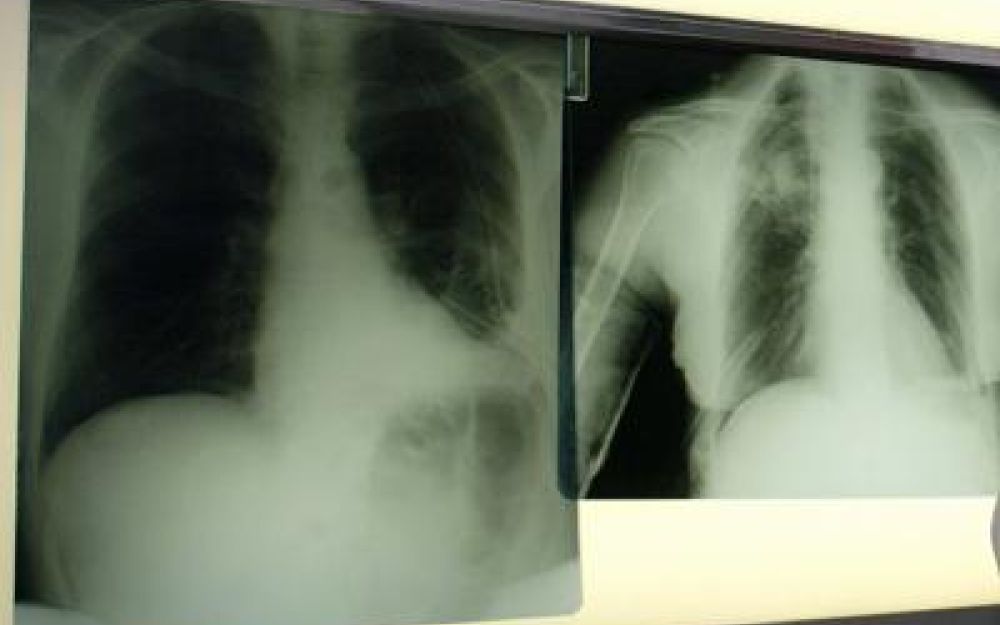

Il virus respiratorio sinciziale colpisce in modo diverso nelle differenti fasce d’età. L’Rsv “è un virus ubiquitario che colpisce praticamente tutti i bambini entro i 2 anni di vita, con possibili reinfezioni nel corso della prima infanzia e financo in età adulta – illustra Paolo Manzoni, professore associato di Pediatria e neonatologia, università di Torino – Se nei soggetti oltre i 2 anni di età il virus causa spesso sintomi simil-influenzali, colpendo per lo più le vie aeree superiori, al contrario una percentuale importante di pazienti con età meno di 2 anni presenta coinvolgimento delle basse vie aeree che può sfociare, nello specifico, nel quadro clinico classico conosciuto come bronchiolite e nelle sue complicanze sia immediate, sia a lungo termine”. Oltre ai neonati prematuri e di età inferiore ai 6 mesi, le popolazioni a rischio di sviluppare una patologia respiratoria grave a seguito di Rsv sono le persone over 60 e quelle immunocompromesse o con patologie preesistenti come il diabete, le malattie cardiache e polmonari, nelle quali il virus può scendere alle vie respiratorie inferiori causando principalmente polmonite.